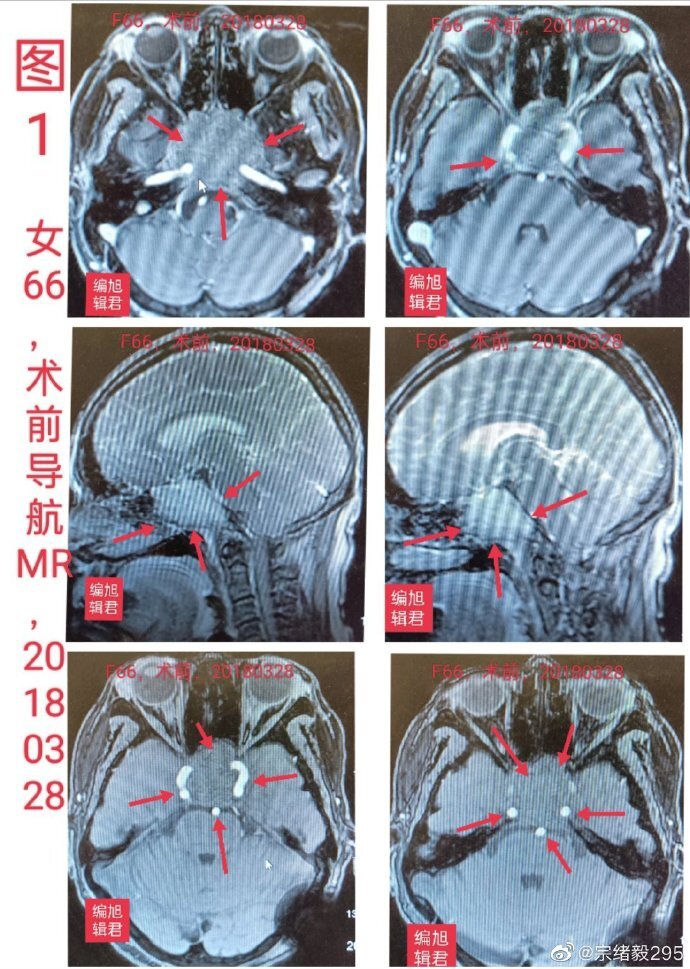

侵袭性垂体瘤mr征象分析影像天地

图片尺寸960x720